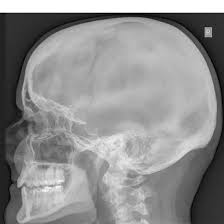

What is an X-Ray Both Mastoids Oblique View?

An X-Ray Both Mastoids Oblique View is a specialized imaging technique that captures angled X-ray images of the mastoid bones located behind both ears.

This view helps in detailed evaluation of the mastoid air cells and surrounding structures to detect infections, fractures, or other abnormalities.How do you prepare for an X-Ray Both Mastoids Oblique View?

An X-Ray Both Mastoids Oblique View Scan is a diagnostic procedure that uses angled X-ray images to examine the mastoid bones behind both ears.

This scan provides detailed visualization of the mastoid air cells and adjacent areas to help identify infections, fractures, or other structural issues..

What can an X-Ray Both Mastoids Oblique View detect?

An X-Ray Both Mastoids Oblique View can detect mastoid infections (mastoiditis), fractures, chronic ear diseases, and abnormalities in the mastoid air cells.

It also helps identify fluid buildup, tumors, or structural deformities affecting the middle and inner ear regions.